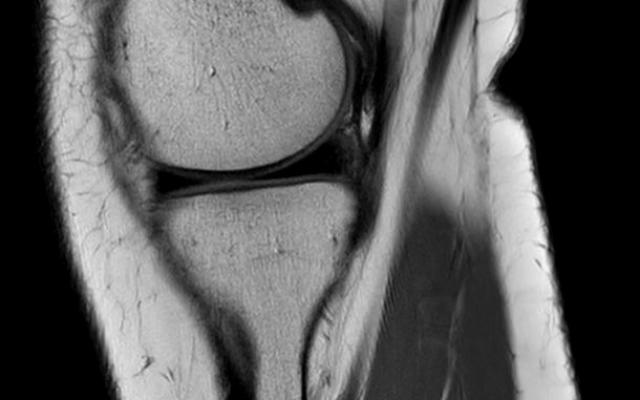

Een 22-jarige vrouw met een blanco voorgeschiedenis werd op de polikliniek Orthopedie gezien vanwege slotklachten van haar linker knie. De nacht ervoor was zij wakker geworden met een extensiebeperking van de knie. Zij vertelde één keer eerder slotverschijnselen te hebben gehad. Er was geen trauma aanwijsbaar. Lichamelijk onderzoek toonde een slanke knie met een verende extensiebeperking van 30° en een flexie van 140°. Er was sprake van drukpijn ter hoogte van de mediale gewrichtsspleet en bij de McMurray-test gaf zij mediaal pijn aan. Behoudens een osteochondroom ter hoogte van de proximale posteromediale tibia werden geen afwijkingen gezien bij het…